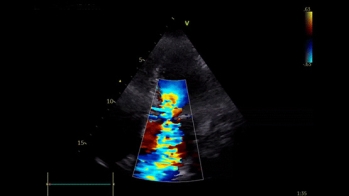

L'ETT montre :

- Flux mitral restrictif